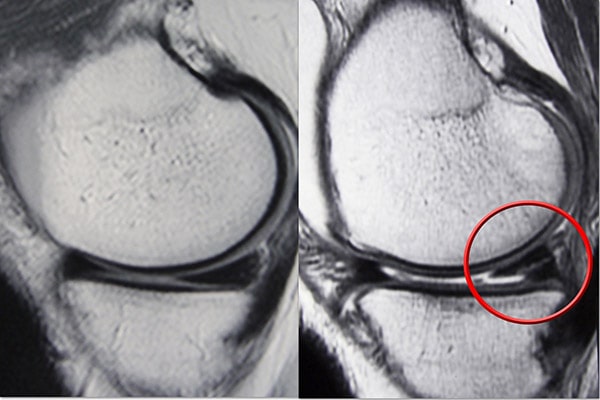

成像測試

由于其他膝蓋受傷也會引起類似的癥狀,您的醫生可能會要求進行影像學檢查以幫助確認診斷。

X光片。 X射線提供致密結構的圖像,例如骨骼。雖然 X 光片不會顯示半月板撕裂,但您的醫生可能會要求檢查膝關節疼痛的其他原因,例如骨關節炎。

磁共振成像 (MRI) 掃描。 MRI 掃描可評估膝關節的軟組織,包括半月板、軟骨、肌腱和韌帶。